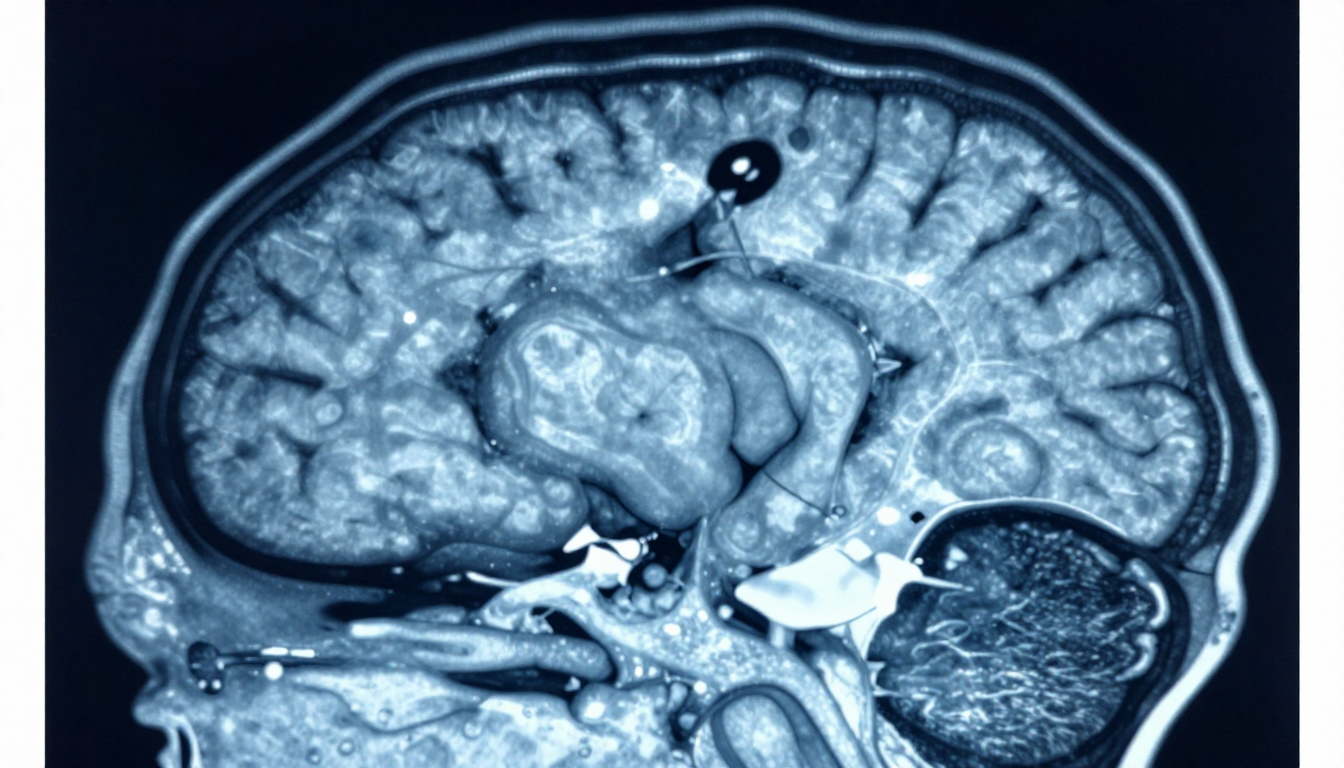

Magnetic Resonance Imaging (MRI) has become one of the most important tools for understanding...

Longitudinal MRI is the practice of comparing brain scans taken at different time points to understand...

Modern brain imaging plays a critical role in understanding neurological conditions...